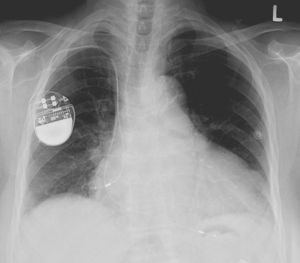

Pacemaker kan hackas och döda användaren Tillverkare får kritik för dålig säkerhet Pacemaker kan hackas och döda användaren Foto: Lucien Monfils / Wikipedia Forskare på den pågående säkerhets/hacking-konferensen Black Hat uppger att pacemakers från företaget Medtronic kan hackas och i värsta fall kan detta hota användarens liv.Enligt forskarna så krypteras inte trafiken när firmwaret på Medtronics pacemakers behöver uppdateras och detta gör det möjligt för obehöriga att installera malware i Medtronics pacemaker. På Black Hat-konferensen i Las Vegas demonstrerade de båda forskarna Billy Rios och Jonathan Butts hur man kunde hacka en maskin som läkare vanligtvis använder för att kontrollera patienters pacemakers efter de implanterats i patienter. Via den maskinen blev det sedan möjligt att installera programvara på pacemakers från Medtronics som i värsta fall skulle kunna göra så att pacemakern gav patienten livshotande stötar. De båda forskarna uppmärksammade Medtronics om säkerhetsproblemet i deras pacemakers redan i januari 2017 och de kritiserar nu företaget för att det fortfarande är möjligt att hacka deras maskiner. arstechnica.com Pryl, Övrigt, pacemaker, hacking, säkerhet, livsfarligt, black hat Världens första online-mord sker i år? Europol varnar för det Tumnagel 18.0° 0 Pacemaker återkallas på grund av att de kan hackas Nästan en halv miljon pacemakers måste uppdateras Tumnagel 27.1° 0 Pacemaker satte dit snubbe för mordbrand Invärtes övervakning Tumnagel 45.2° 0 12.3° 0 Wille Wilhelmsson Wille Wilhelmsson